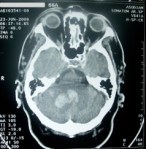

Tomografía axial computada (TAC): La tomografía axial computarizada (TAC), o tomografía computarizada (TC), también denominada escáner, es una técnica de imagen médica que utiliza radiación X para obtener cortes o secciones de objetos anatómicos con fines diagnósticos.